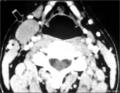

В диагностике боковой кисты шеи большое значение имеет КТ в режиме контрастирования, которая позволяет уточнить локализацию, топографические особенности ее расположения, размеры, плотность содержимого и состояние региональных лимфатических узлов.

На КТ справа по переднебоковой поверхности шеи кпереди от сосудисто-нервного пучка, медиальнее от грудино-ключично-сосцевидной мышцы обозревается плотная тканевая структура которая проецируется на уровне подъязычной кости и щитовидного хряща. Размеры 4х2,5 см. Сонные артерии и внутренняя яремная вена оттеснены медиально.

Заключение: плотная тканевая структура по переднебоковой поверхности шеи (с права) расположенной кпереди от сосудисто-нервного пучка шеи (по структуре очевидно можно предполагать наличие смешенной доброкачественной опухоли).